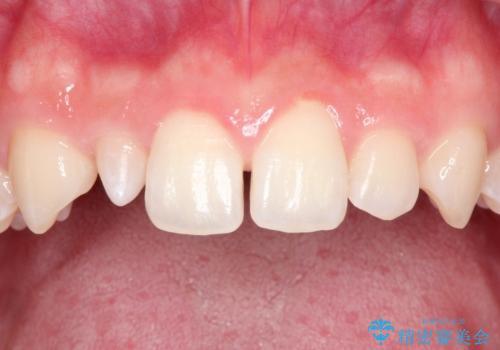

- 上の歯の隙間が気になるとのことで来院されました。

上顎の正中に隙間があり、右上の2番目の歯が通常の歯より小さい矮小歯でした。

正中の隙間をインビザライン矯正で閉鎖して、右上の2番目の歯にはセラミックを装着する計画としました。